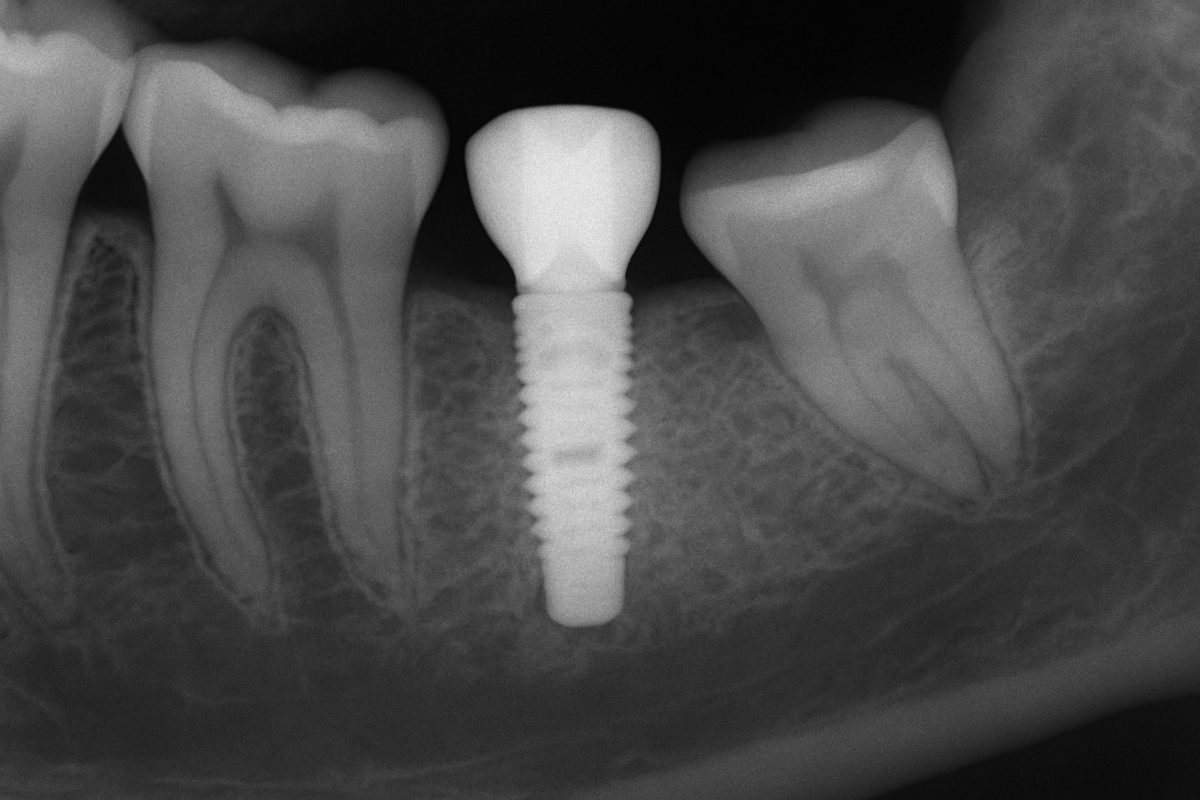

An x-ray showing a tooth implant graft integrating into the jawbone, highlighting the increased bone density around the implant site. No text on the image.